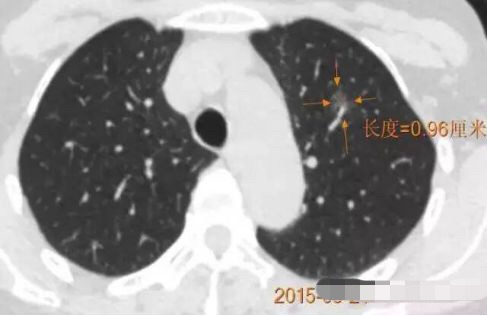

随访3年,GGO直径基本没有变化

2013年12月

2014年7月

2015年5月

2016年10月